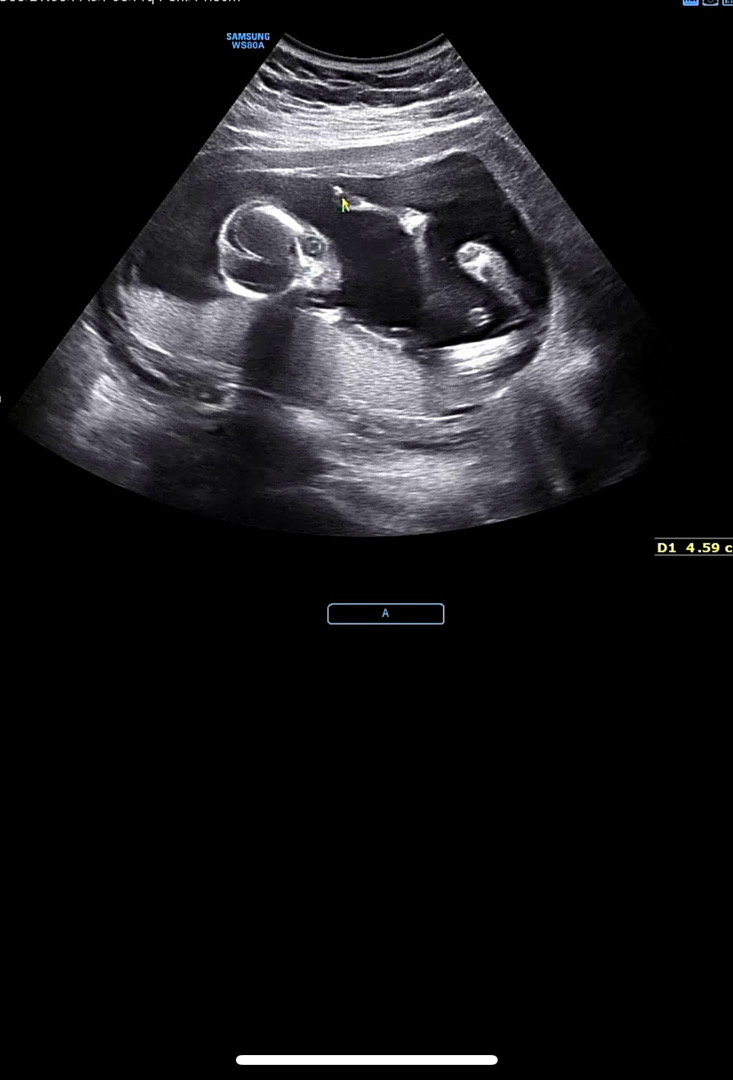

뇌가 하트뿅뿅♡

외계인 보고와떠요🤣🤣

저두 오늘 외계인 사진보고왔어요ㅋㅋㅋㅋ 초음파 사진 찍으면 부모님들께 보내드리는데 이번건 좀 무섭게 찍혀서 보내드리기 망설여지더라구요ㅠㅋㅋㅋ

이렇게도 찍힐수있다는걸 어른들은 잘 모르시니까 놀라실수도있을것같아용ㅋㅋㅋㅋ🤣

뇌와 안구가 예쁘게 잘 만들어졌네요. 아기 낳으면 눈이 참 예쁘겠어요😀